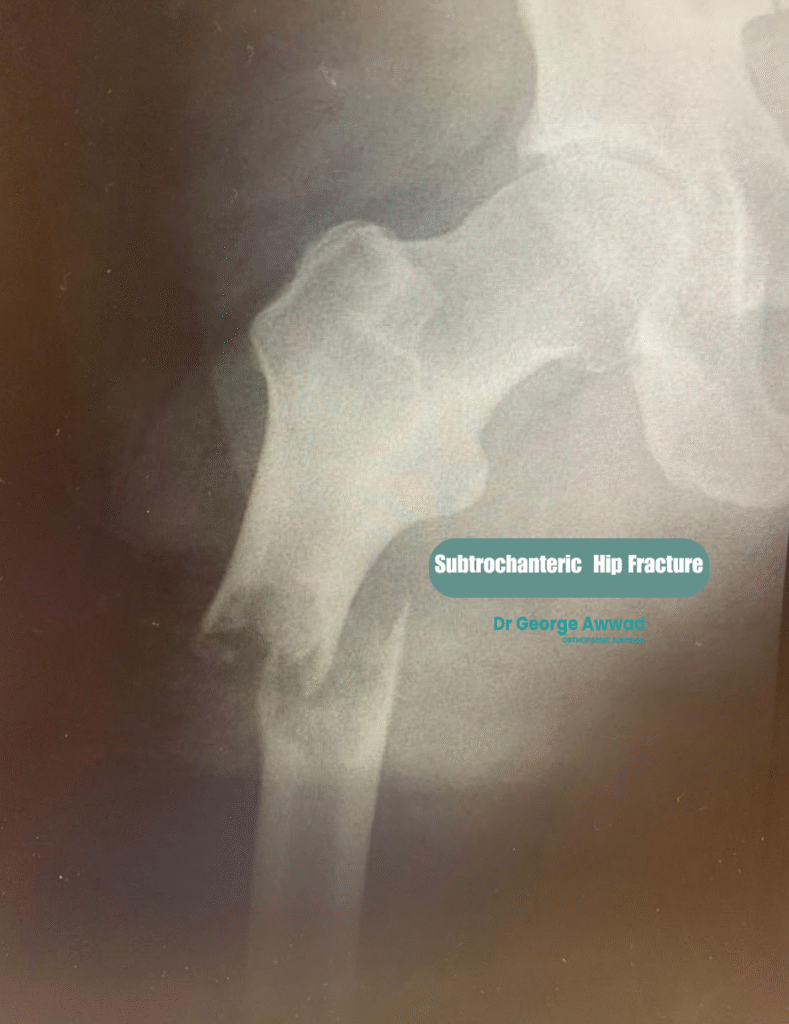

3. Subtrochanteric fractures

- Less common

- Often caused by high-energy trauma or underlying bone pathology

- May require more complex surgical fixation techniques due to the powerful muscles acting on this region

Certain types of hip fractures, such as displaced femoral neck fractures or unstable subtrochanteric fractures, typically do not heal well without surgery and carry a high risk of non-union or avascular necrosis. -